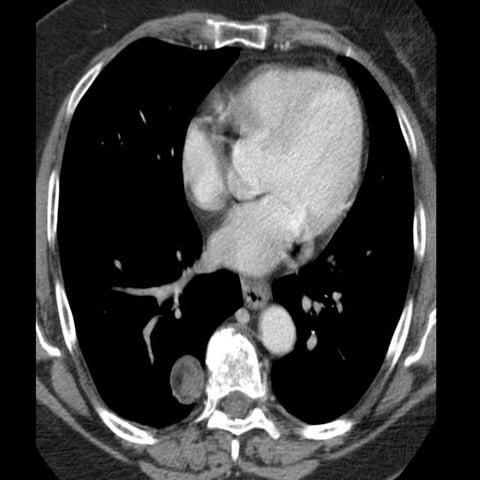

40 year old